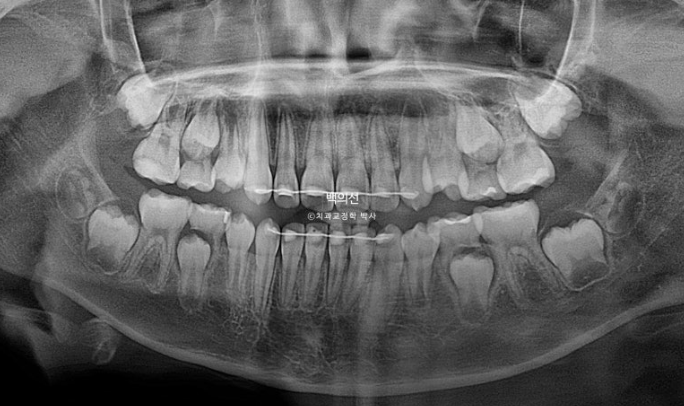

엑스레이에서 아래턱의 골격적 비대칭으로 진단이 되었습니다.

치근평행도는 좋습니다.

치료 마무리 시점 남아있는 유치는 4개이고 추후 자연스럽게 빠지고 나면 영구치가 적절하게 올라올 것 입니다.

현재는 아래턱 위치가 안정적이라 가철식 유지장치 없이 고저식 철사 유지장치만 붙인 상태로 유지중이고 성장이 끝날때까지 1년 간격으로 정기체크가 필요합니다.